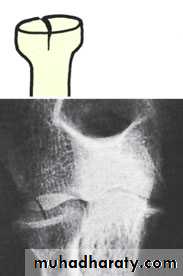

This fracture is sometimes missed, but tenderness on pressure over the radial head and pain on pronation and supination should suggest the diagnosis.X-ray

Three types of fracture are identified and classified by Mason as:Type I An undisplaced vertical split in the radial head.

Type II A displaced single fragment of the head.

Type III The head broken into several fragments (comminuted).